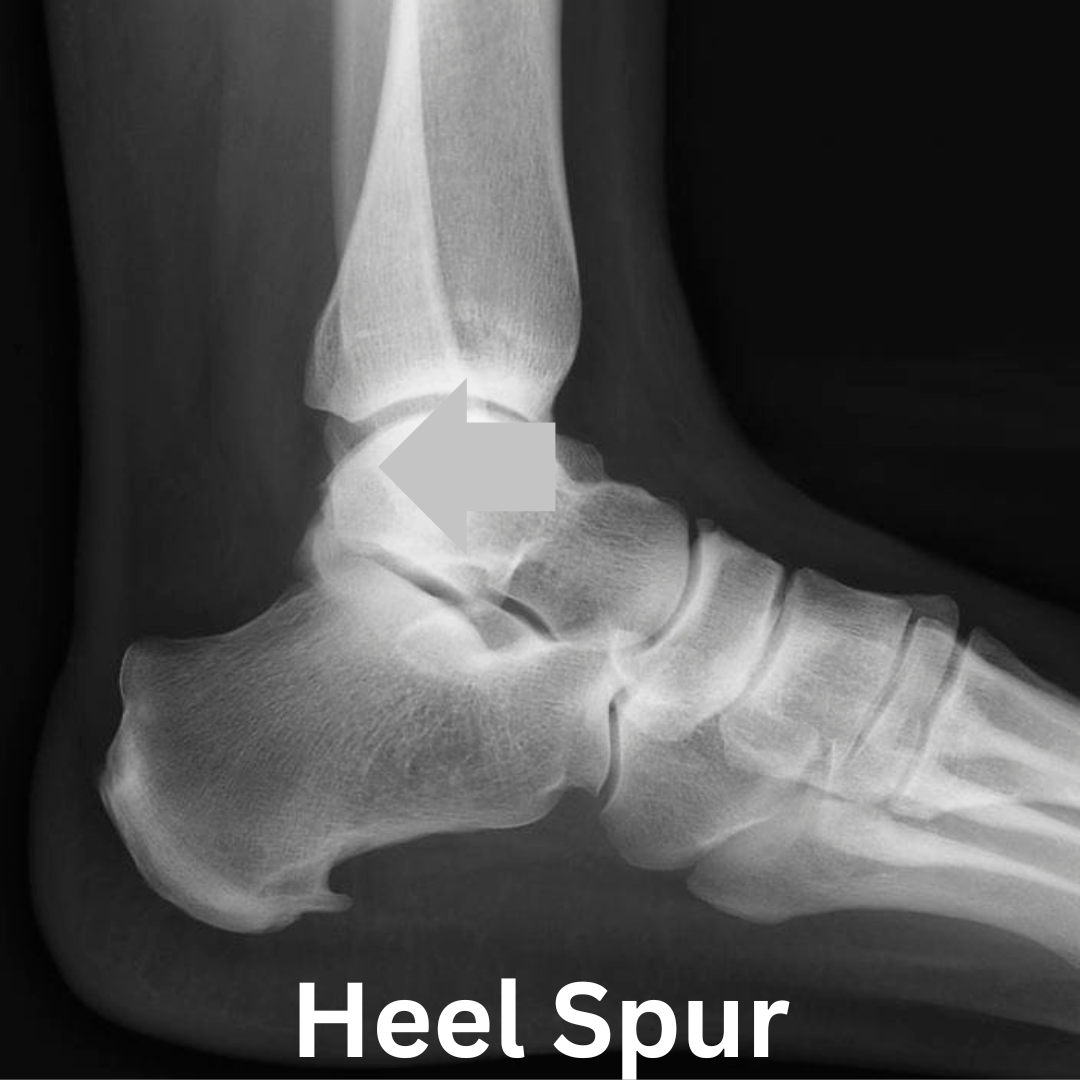

A heel spur is a bony projection from the heel bone to the fascia to help with the connection to the fascia and improve strength and reduce strain and can be very painful. An important note many of you will have heel spurs that don’t cause any pain from repair of previous plantar fasciitis damage or stress on the foot, this can be up to 40% of you ( Michelsson et al. 2005).

Painful heel spurs in lots of cases are linked to plantar fasciitis damage and the body trying to heal itself. However if you have no pain first thing in the morning and only pain in the evening after you have being moving and stressing your foot all day it points towards heel spurs and 20% of plantar fasciitis sufferers.

As your Plantar Fascia stiffens, it increases the tensile force on the attachment point on the heel. To cope with this additional stress your body remoulds the bone around the area, which is what actually produces the spurs. A reason for this is a protective mechanism to stop the fascia bending as much, this will alter how you stand and walk.

The size of the spur also has an impact, but not as you may think, it can cause compression of your lateral plantar nerve. This compression causes pain and a burning sensation, and long term compression causes muscle wastage in the heel area ( Chundru et al 2008 ).